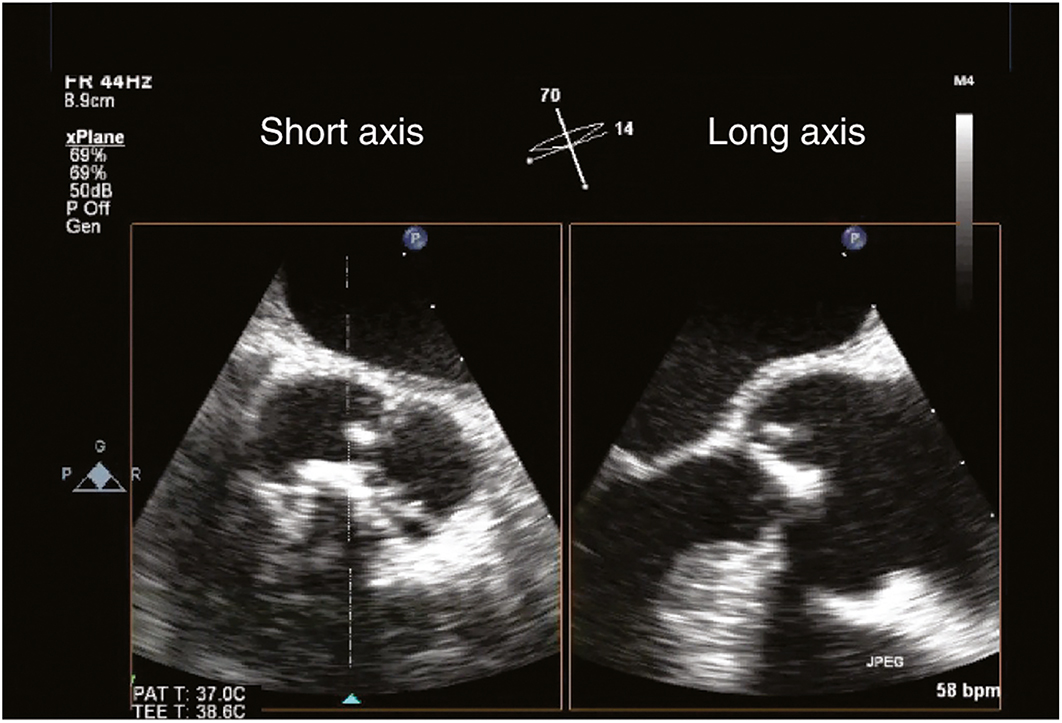

Echocardiographic criteria for AS include 2D or 3D imaging demonstrating limited AV cusp motion, a small orifice, and left ventricular concentric hypertrophy (Figure 7.16; Video 7.1). Doppler examination reveals a turbulent, high-velocity jet across the AV, and color flow Doppler demonstrates a turbulent, mosaic-appearing color map. The gradient across the AV measured at cardiac catheterization is different from that measured by echocardiography as discussed previously. Quantification of the Doppler-derived AS pressure gradient relies on the modified Bernoulli equation.

Figure 7.16.: Transesophageal Echocardiographic Findings of Moderate Aortic Stenosis (Midesophageal Aortic Valve [av] Short-Axis View [left] and Long-Axis View [right]).

Transesophageal echocardiographic findings of moderate aortic stenosis (midesophageal aortic valve [AV] short-axis view [left] and long-axis view [right]). The AV cusps are calcified and demonstrate limited systolic excursion.